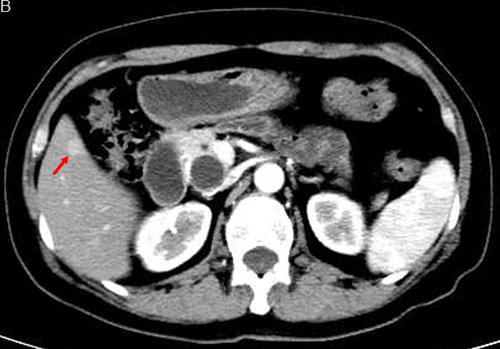

According to the imaging findings from before and after therapy, excluding the one case that was lost to follow-up, there were 11 PR cases (42.3%), 10 SD cases (38.5%), 5 PD cases (19.2%), and no CR cases. The efficacy rate was 42.3% (Figures 1 and 2).

Figure 1: TACE in a 59-year-old female with multiple liver metastases form pancreatic neuroendocrine tumor. A. Contrast-enhanced CT before TACE revealed a segment 6 hypovascular liver metastasis in the arterial phase (arrow) B. contrast-enhanced CT showed a significant decrease in the lesion at 6 months after treatment (arrow).